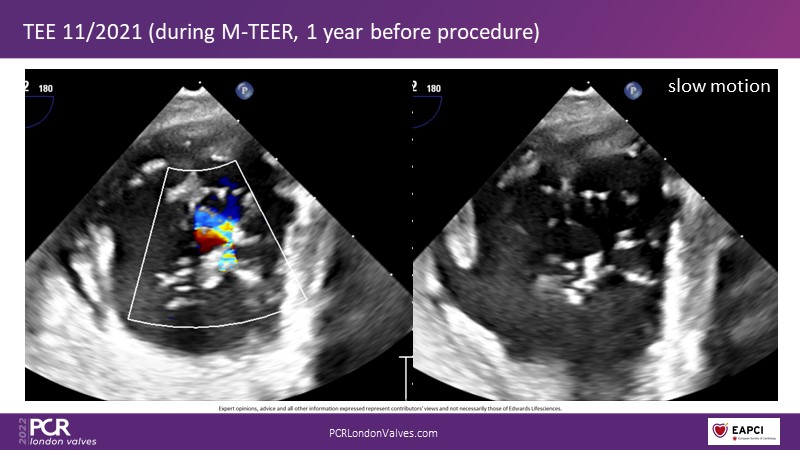

This innovative session takes you through the patient selection and anatomical characteristics when selecting amongst the different transcatheter options to treat tricuspid regurgitation, followed by a recorded demonstration using the PASCAL Precision repair system.